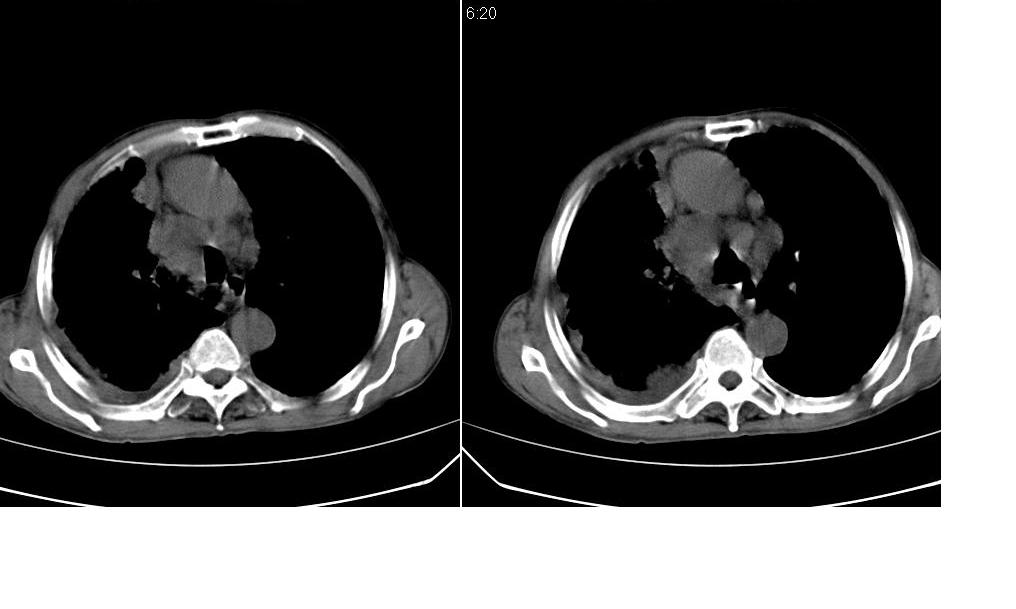

以下是引用zsl6918在2008-5-3 19:53:00的发言:[br]右肺中心型肺癌并纵隔淋巴结转移,胸膜转移,右肺癌性淋巴管炎。

以下是引用liuyue在2008-5-3 20:49:00的发言:[br]1.右侧中心型肺癌伴双肺转移瘤、纵隔淋巴结转移、右侧胸腔积液(侵及胸膜所致可能性大)。[br]2.右肺阻塞性肺炎,癌性淋巴管炎不除外。